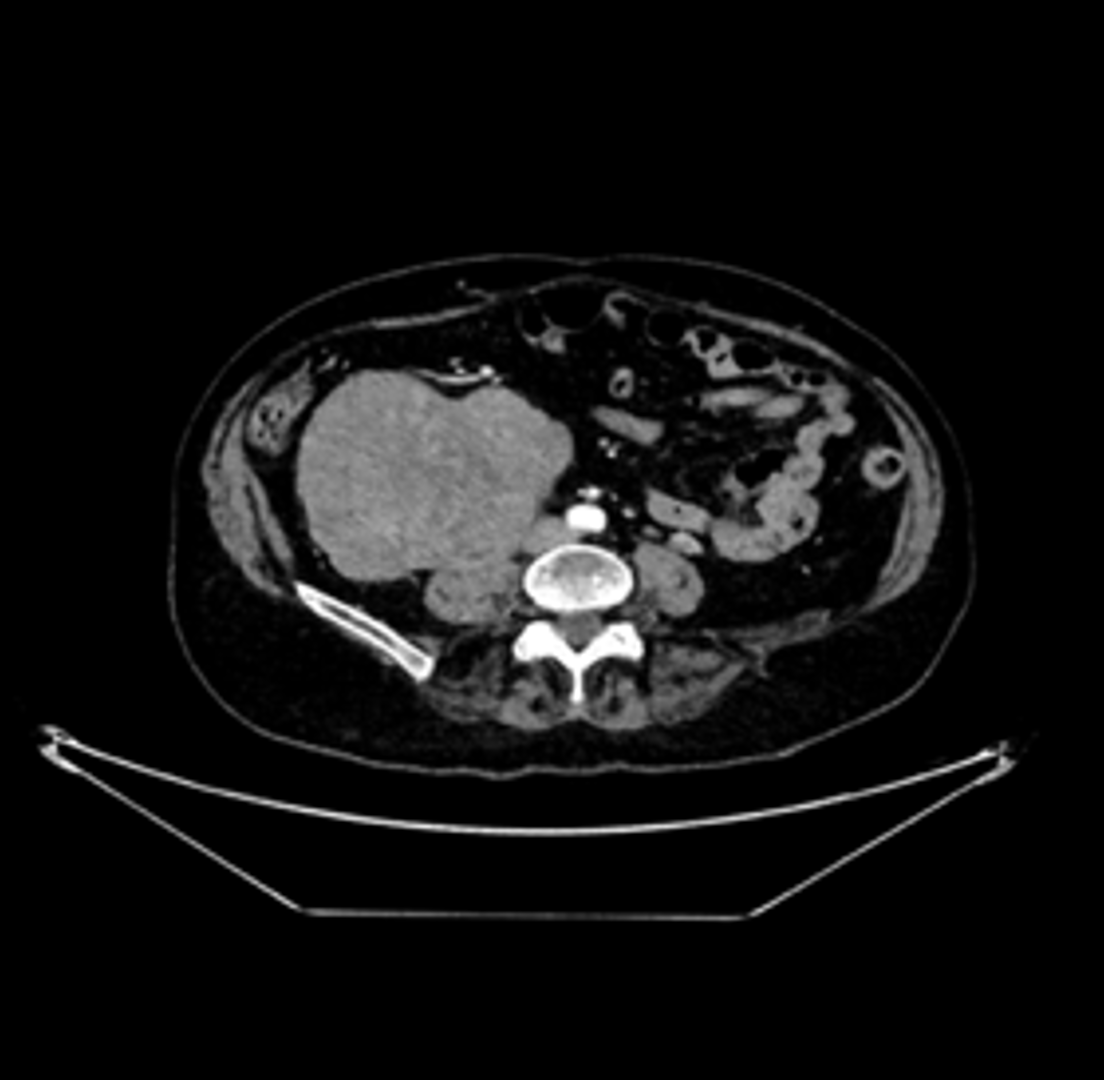

TC de abdomen con contraste en ventana de partes blandas